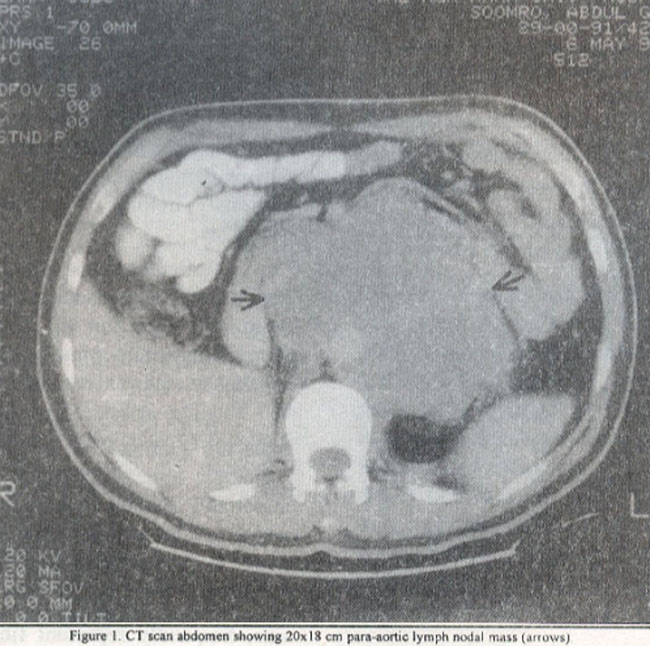

One year later, he presented with upper abdominal pain and weight loss. Examination revealed large upper abdominal mass. Tumor markers were 13-HCG 109.5 mIU/ml (0-5), AFP 6.9 lU/mi (0.5-5.0), and LDH 11,566 lU/L (253-548). A CT scan showed 20x18 cm para-aortic lymph nodal mass (Figure 1).